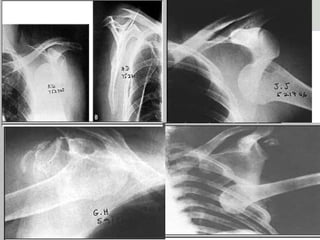

Radiografia

LUXAÇÃO ACROMIOCLAVICULAR

Rx para aticulação acromioclavicular sem tração

Rx para articulação acromioclavicular com tração